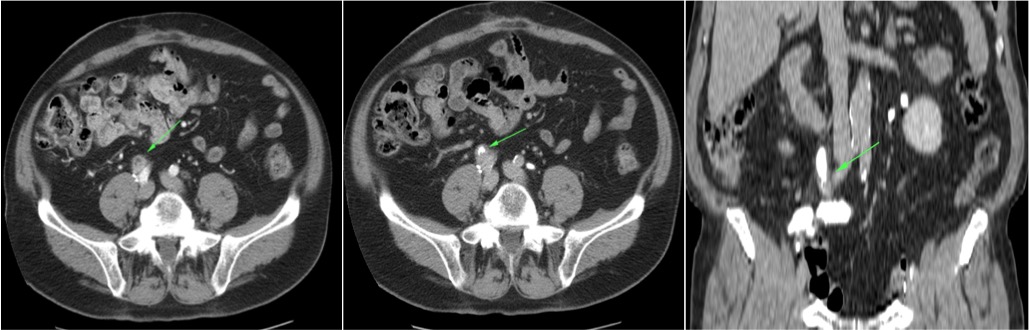

CASO CLÍNICO: Recopilatoción.

Paciente de 59 años con antecedentes personales de Cá de vejiga.

Se le realiza una Uro-Tc por seguimiento al año, aunque en esta ocasión el paciente refiere episodio de hematuria.

Tras el tratamiento de la recidiva y nefrostomía para la hidroureteronefrosis, vuelve acudir al hospital a los 9 meses por episodio de dolor en FD y malestar general. Se realiza una ecografía de urgencias.

Se realiza nueva TC bifásico abdominopélvio y Uro TC.